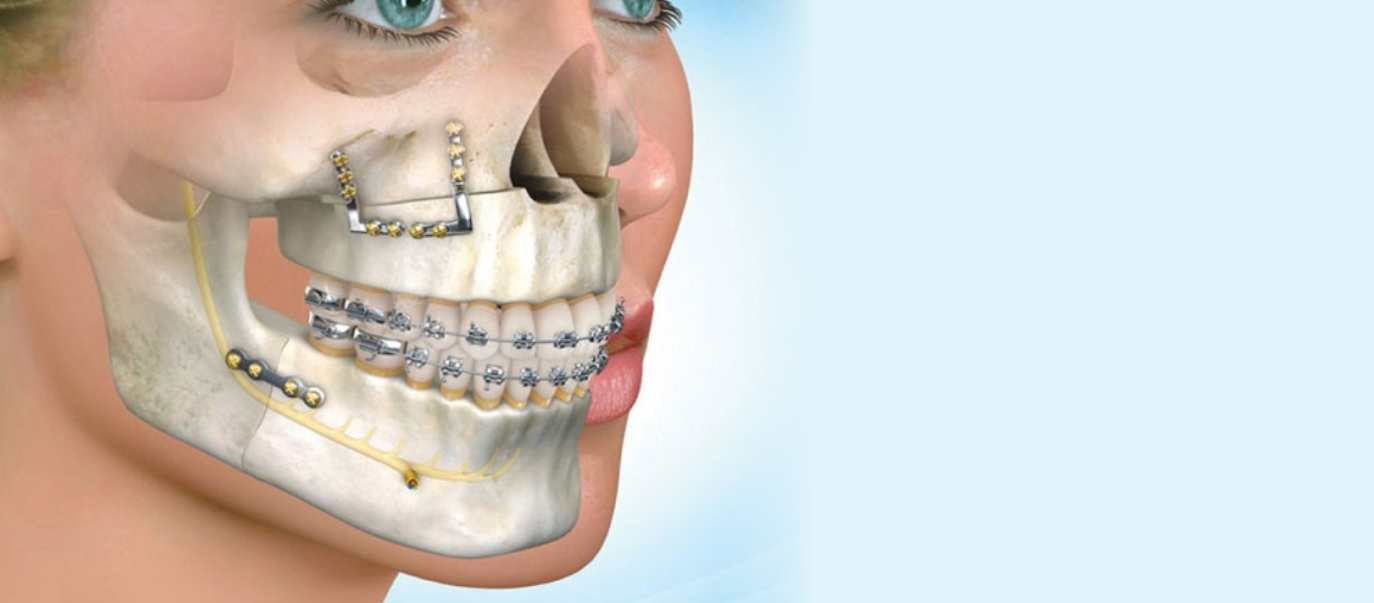

Cerrahi Tedaviler

Ağız, Diş ve Çene Cerrahisinde yapılan tedaviler daha çok gömük yirmi yaş çekimi olarak düşünülmektedir.

Devamını Oku